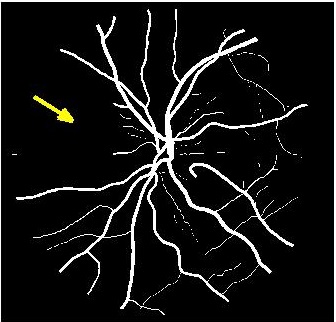

Figure 3 shows super resolution results for retinal fundus images. The image has been downsampled by a factor of each along rows and columns, and the original image is obtained using different methods. shows better reconstruction results (Fig. 3 (d) )than most competing methods. However the reconstruction is a bit blurry for small retinal vessels using as indicated by the yellow arrow. This defect is overcome using the proposed architecture (Fig. 3 (c) ), thus justifying the use of progressive GANs over saliency maps for image super resolution.

Figure 4 (a) shows an example retinal image followed by its ground truth manual segmentation in Figure 4 (b). Figure 4 (c) shows segmentation result for scaling factor when using the original HR images to train the U-Net followed by the results when trained on the super resolved images generated by , (Figure 4 (d)), (Figure 4 (e)), (Figure 4 (f)), SR-RF (Figure 4 (g)), SSR (Figure 4 (h)) and (Figure 4 (i)). Obviously the results from provide results most similar to those of HR images. This is also validated by the quantitative results in Table 3. The areas where different methods are unable to obtain accurate segmentation are highlighted by yellow arrows. Due to poor quality of super resolved images most of the methods do not segment the finer vasculature structures, while SSR and SR-RF are unable to segment some of the major arteries. Importantly, our method performs much better than the low resolution image () which performs poorly due to low resolution.